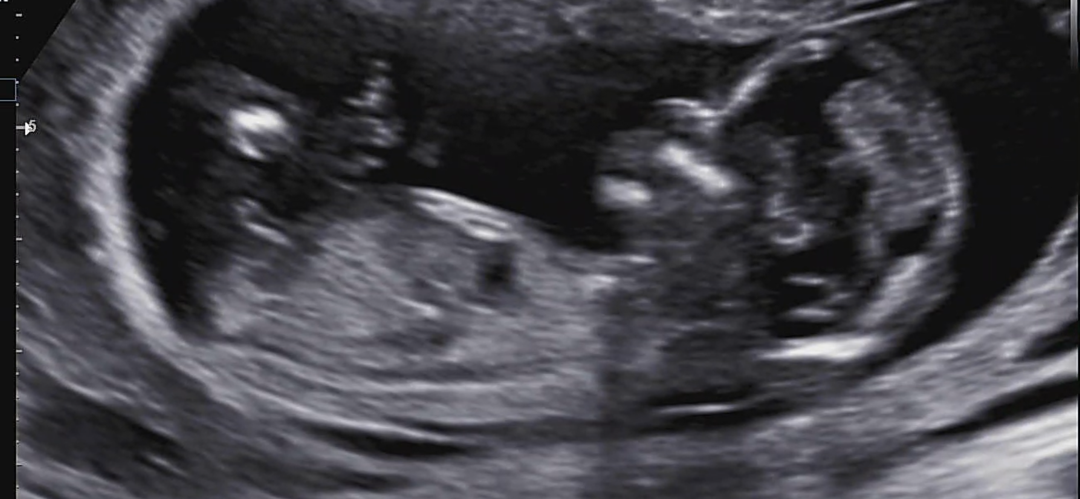

13주0일 검진다녀왔는데 병원에서 아무런 말씀이 없으셔서 유난떨며 물어보기도 조금 조심스러워서요 여기도 이런글 안좋아하시는거 알지만 조심스럽게 올려보아요! 한마디씩만 해주고 가셔요

끝이 살짝 올라간게 아들각도 같아요